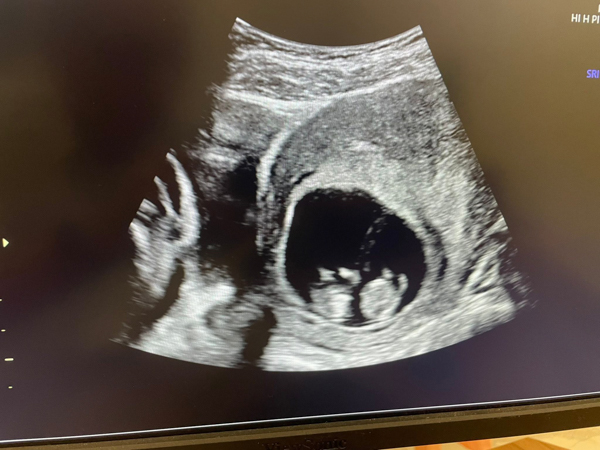

今天懷孕10+周

胎兒大小,心跳及活動力都好棒棒👍

於7周超音波檢查發現有雙胞胎妊娠🧐

目前兩位寶寶都充滿活力💖